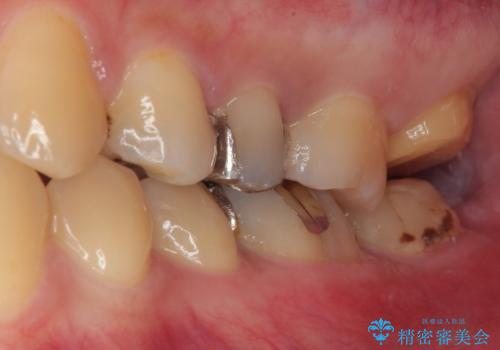

- 銀歯が何度も外れるとのことで来院された患者様です。

保険の金属の詰め物(メタルインレー)が適合性が悪い状態で入っていたので、詰め物も大きかったのでオールセラミッククラウンでの治療をご提案しました。

拡大鏡視野下で、金属の詰め物(メタルインレー)、虫歯の除去を行い、オールセラミッククラウンに適した形に整えました。